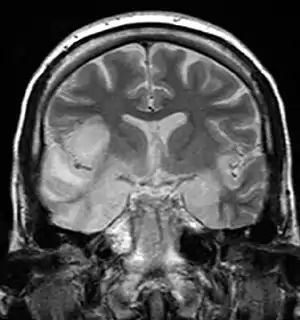

Hemorragia também é incomum, porém encontrada nas encefalites por Herpes e por amebas. Ressonância magnética oferece melhor resolução, mas o diagnóstico é clínico: paciente com febre, vômitos, alteração da consciência ou do comportamento devem ser investigados para encefalites sem perda de tempo. Em pacientes com encefalite por herpes simples, o eletrencefalógrafo pode mostrar ondas afiadas em um ou ambos os lóbulos temporais.